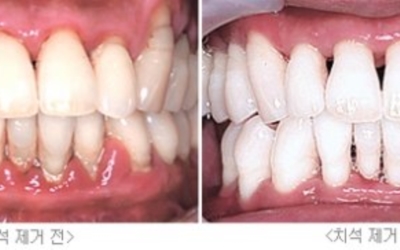

잇몸에 붓기가 생기고 통증이 발생하는 경우의 대부분은 우리의 치은과 관련이 있어요. 치은이란, 잇몸을 말하고 이곳에 염증이 생기면 이를 치은염이라고 합니다.흔히 치아 관리를 제대로 하지 않아 플라그라는 세균막이 생기며 석회화 된 치석이 잇몸과 치아 사이를 벌어지게 하는데 이 부분에 세균이 침투하고 염증을 발생시키면서 치은염으로 발전하게 돼요.

양치질을 할 때 피가 나고 입 냄새가 심해질 수 있으며 식사를 할 때 불편함을 느끼는 등 잇몸이 붓고 아플때 치은염을 의심해볼 수 있어요. 치은염을 계속 방치하게 될 경우 치아 주위 조직에 까지 염증이 번지는 치주염으로 발전할 수 있으니 잇몸에 이상을 장기간 느끼신다면 치과에 방문해 진단을 받아보셔야 합니다.